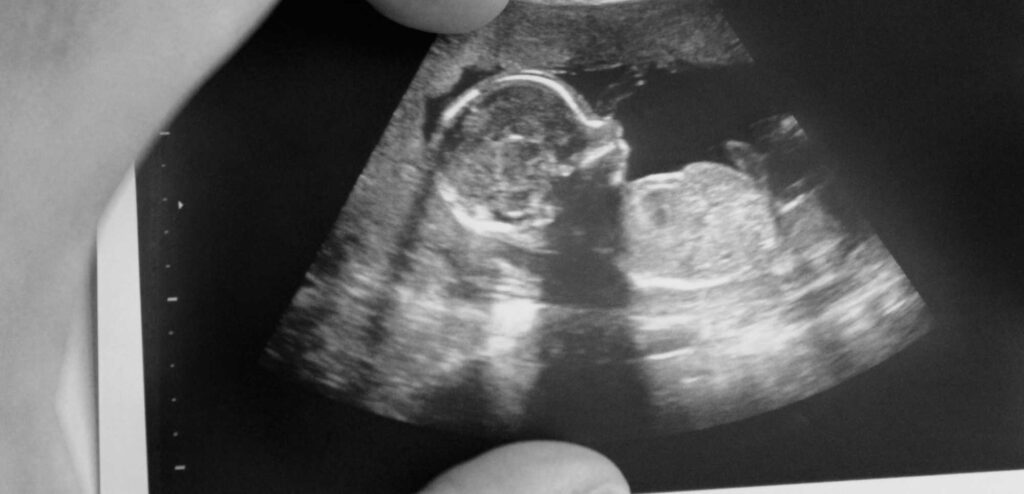

Mielomeningocele: diagnóstico precoce por ultrassom

A mielomeningocele é uma condição congênita que afeta o desenvolvimento da medula espinhal e das vértebras do feto. Embora seja considerada uma malformação grave, os avanços na medicina fetal, especialmente no diagnóstico por ultrassonografia, têm oferecido novas possibilidades para melhorar a qualidade de vida dos bebês diagnosticados ainda no útero.